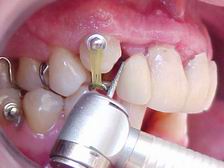

Preparação para instalação do "aparelho ortodôntico" (canino reconstruído em resina rápida autopolimerizável, retida por fio metálico sobre raiz residual)

Início do tratamento ortodôntico. Com a extrusão do canino estaremos induzindo ao nivelamento ósseo para a instalação de implante nesse local.